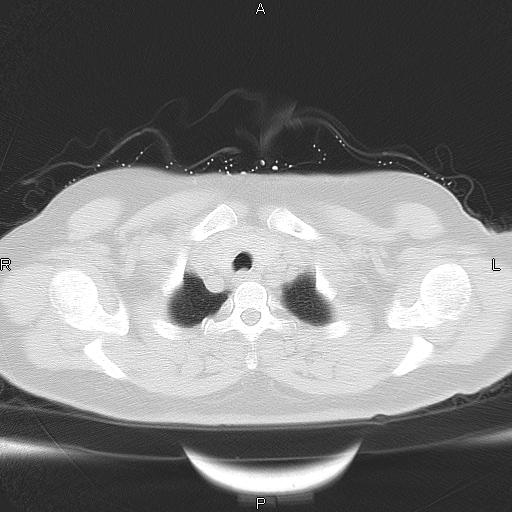

女、63Y 双眼睑下垂,早轻晚重。 胸腺瘤???

结果胸腺瘤